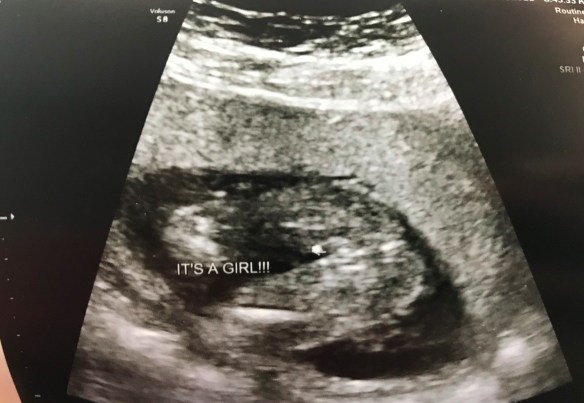

BABY!!!!

Well, after 9 long months of waiting, we finally got the call that our sweet baby girl was ready to meet us. We spent 21 LONG hours of pacing the halls of the labor and delivery ward of the hospital until the moment came. We gowned up and headed into the delivery room where I got to help deliver our sweet baby girl and Scott got to cut the cord, and at 6 o’clock on a Sunday evening, we finally got to hold that sweet 7lbs 11oz baby in our arms! We instantly fell in love with Mila Jolie Achen. We immediately began bonding to make up for the nine months that I didn’t get to hold her. It was especially wonderful thanks to the beauty of induced lactation (shout out to Kim Smetzer at Mountain View Hospital for her expertise on this matter) which took lots of work leading up to that moment, but totally worth every minute. Over the next few days we bonded with our little Mila Jolie in the hospital (coincidentally in the same room we spent weeks in during the whole ordeal after Liam was born) while a few doors down Mila’s womb-mate recovered. The L&D nurses at Mountain View were absolutely amazing. We were all so well taken care of.